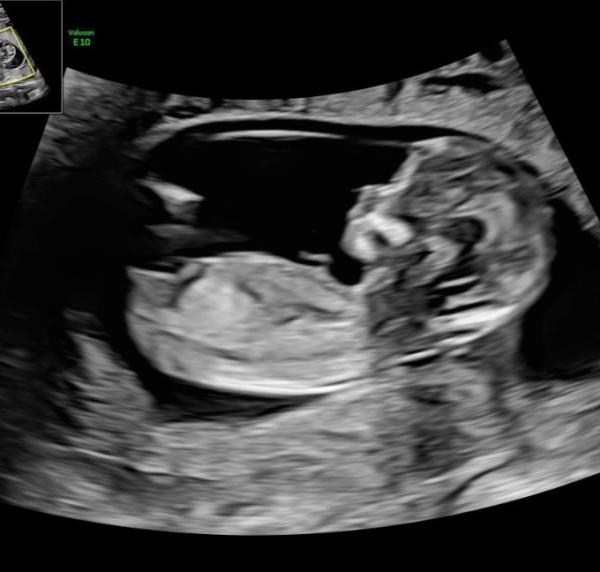

Vielen Dank für die ganzen Antworten von euch, ich freu mich, dass so viele gern hin und her spekulieren wie ich ich habe alles mit großem Interesse gelesen Ich habe bei einigen gelesen, dass ihr morgen einen Termin habt. Würdet ihr denn gern Bescheid geben ob ihr was in Erfahrung gebracht habt Mir wurde bei der nackenfaltenmessung gestern ein vorsichtiger Verdacht mitgeteilt - vermutlich ein Mädchen jetzt muss ich mich bis 01.02. gedulden ich häng mal ein Foto mit dran falls wer mit gucken möchte

Bild zu